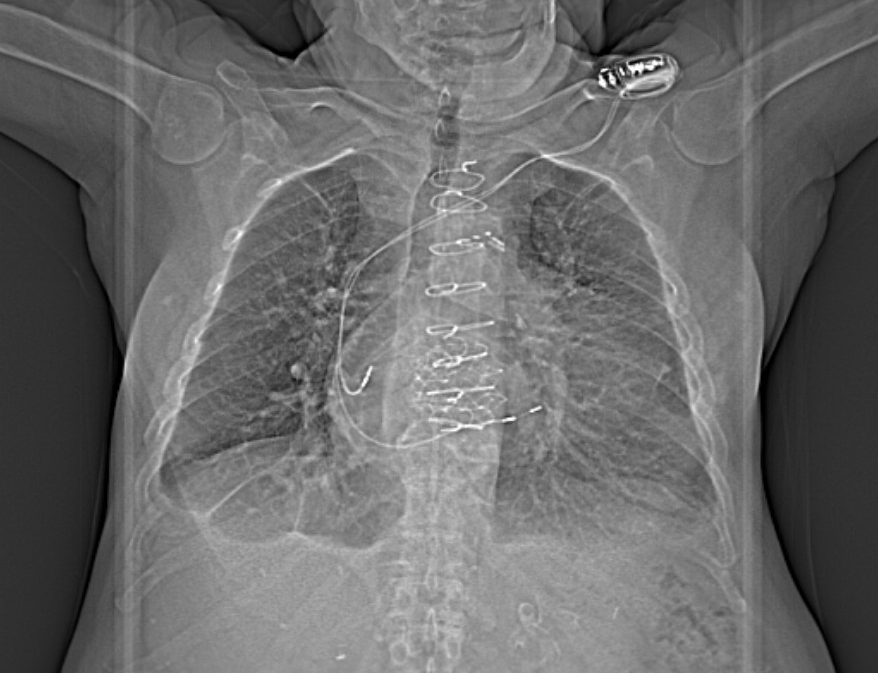

NI DCM. EF 25%. #ECG #EPeeps #CardioTwitter @AdolfoFontenla @jvillacastin @ALFIEEP1 @EF_Cardiaca @Ed_Gerst @Arritmias_HRC @FellowEP @syamkumarmd @DrRoderickTung @ArritmiasHUSC